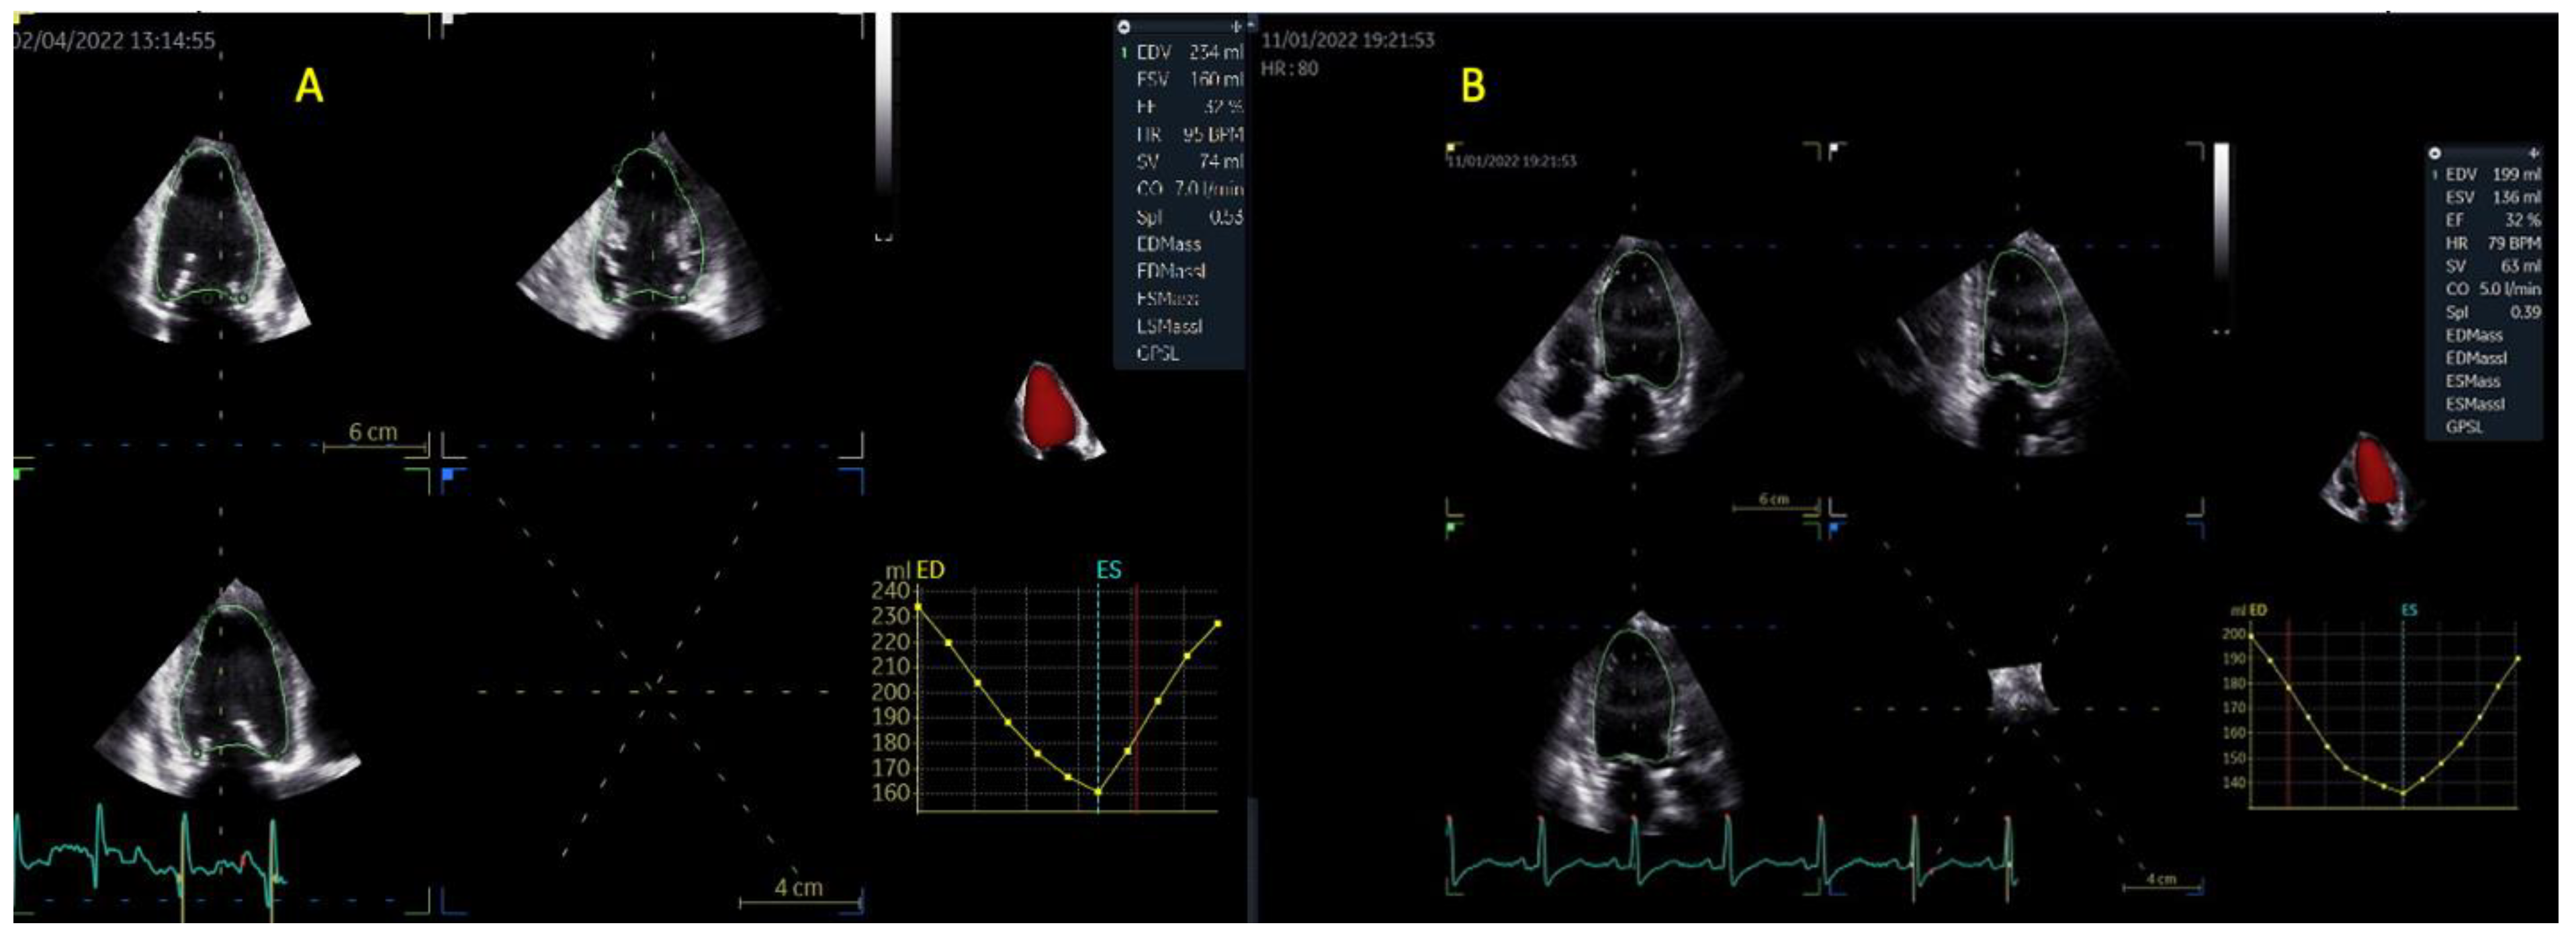

| 3D LVEDV (mL) | 214 ± 56 | 256 ± 112 | >0.05 |

| 3D LVESV (mL) | 152 ± 51 | 191 ± 101 | >0.05 |

| 3D LVSV (mL) | 60 ± 14 | 64 ± 21 | 0.3 |

| 3D LVEF (%) | 31 ± 9 | 27 ± 8 | 0.1 |